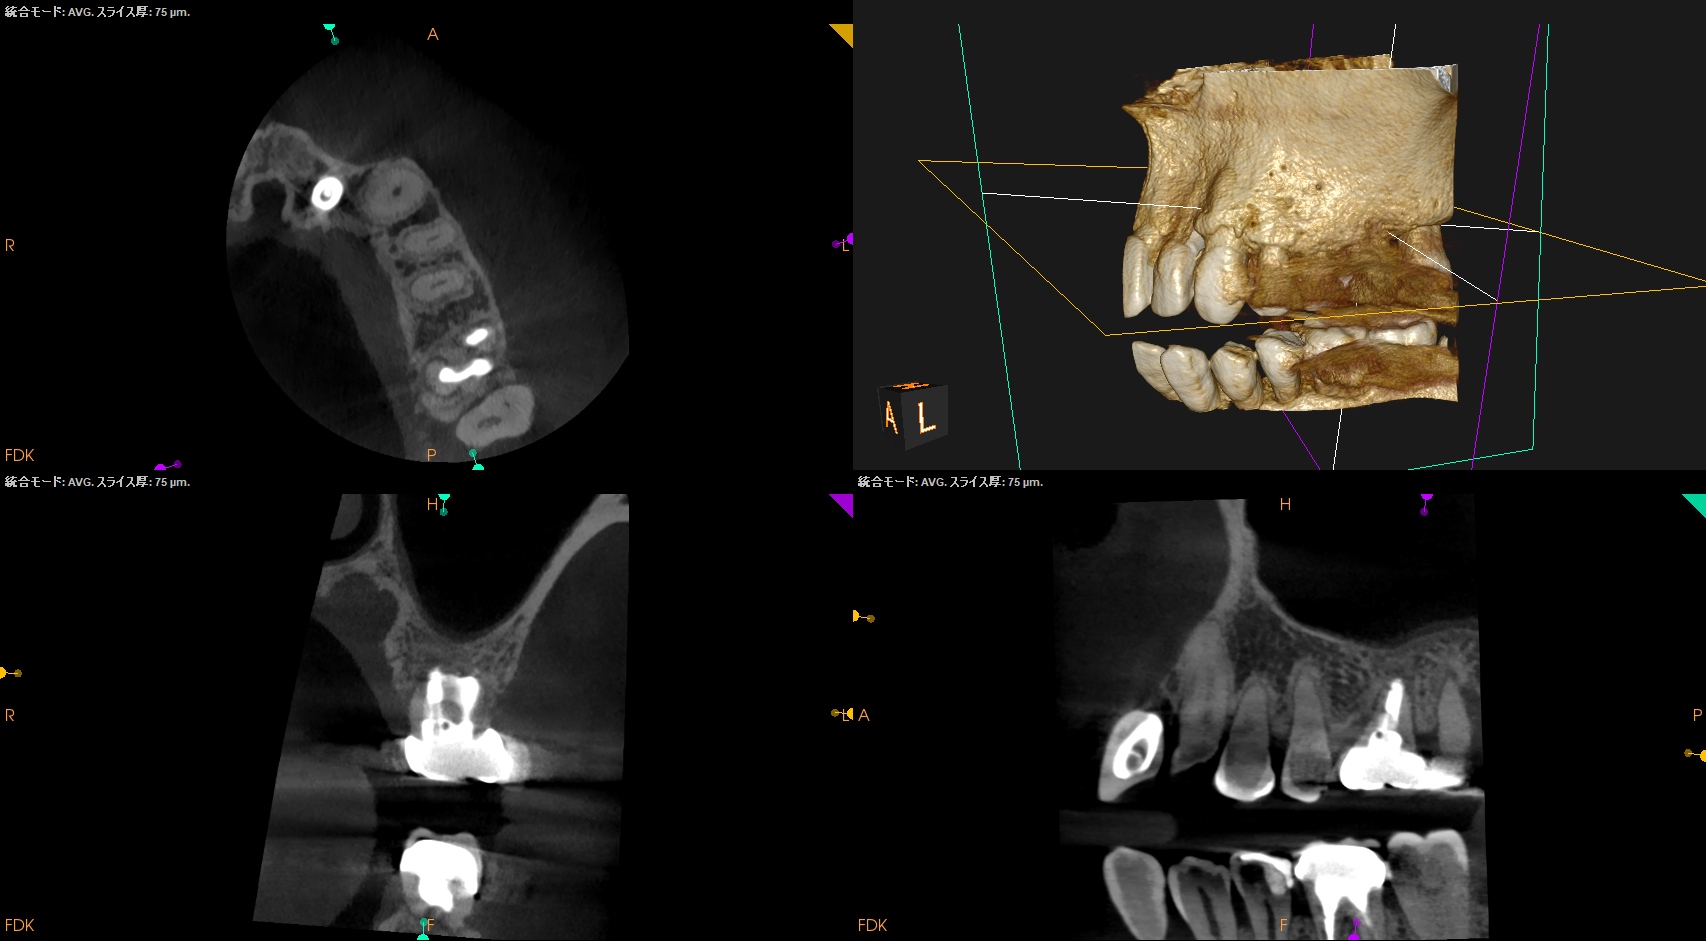

PA, CBCTも撮影した。

#14

MB

DB

P

#14と同じような症状がある#2,5であるが、

#2

#5

B

初診時と比較した。

問題が劇的に解決していることがわかる。